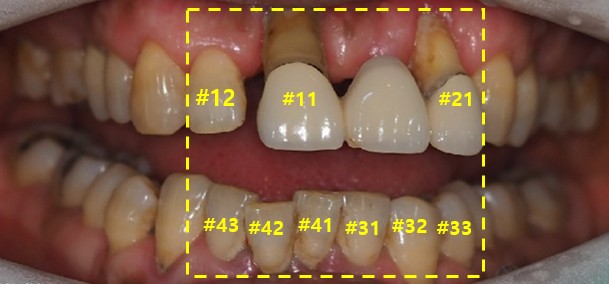

다시 환자분의 사진을 한번 보도록 하겠습니다.

상악 #15 12 11 21 치아들은 임플란트 치료를 진행했습니다.

하악 표기된 치아들은 살리는 방향으로 해서 신경치료 후 크라운 보철 치료함께 하였습니다.